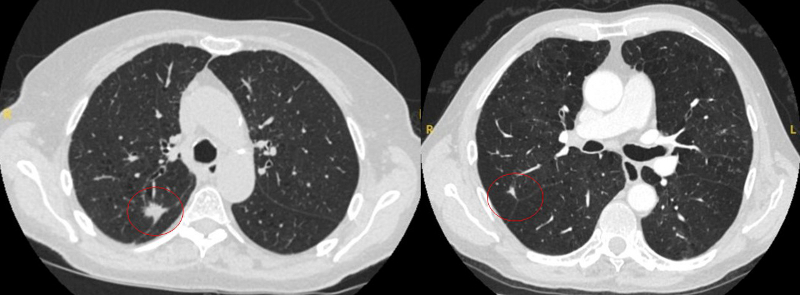

Cortes de tomografia computadorizada (TC) de dois casos com nódulos perifissurais benignos. Observe as margens lisas e a fissura adjacente normal e intacta

Do acervo de Dr. George Tsaknis, MD, PhD, FRCP (Londres), MRQA, MAcadMEd, PGCert; usado com permissão